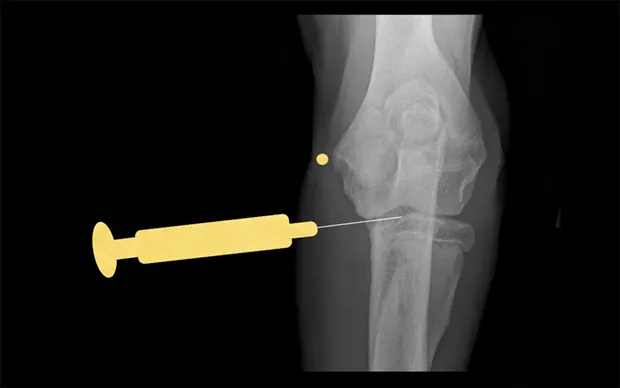

Stifle

Place the patient in dorsal recumbency with the stifle flexed to a 90° angle. The fat pad of this joint may hinder aspiration of joint fluid. Insert a 22-gauge, 1.5-inch needle just medial or lateral to the patellar ligament and about half the distance from the tibial crest to the patella. The needle should aim toward the intercondylar notch.

Lateral view of stifle. Insert the needle medial or lateral to the patellar ligament toward the intercondylar notch.